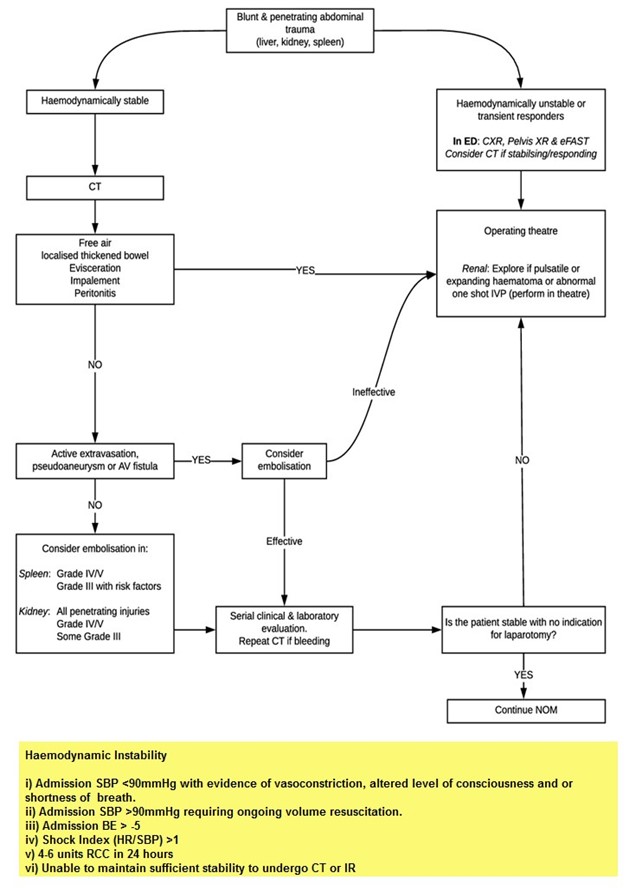

Blunt abdominal trauma is more challenging than penetrating trauma, where the decision to operate is usually straightforward. All abdominal trauma is managed one of three ways:

- Operative

- Non-operative management (NOM) with IR

- NOM without IR.

- The following are the commonest indications for an immediate laparotomy:

- Unstable patient with positive FAST

- Peritonitis

- Unstable patient with free fluid on CT

- Hollow viscus injury

- Retained weapon

- Gunshot wound

- Evisceration.

- A laparotomy should be strongly considered when free fluid is present in the absence of solid visceral injury.